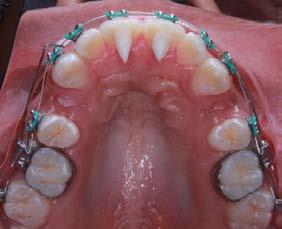

Caso clínico: paciente femenino de 19 años, patrón dolicofacial, perfil convexo, clase II esqueletal debido a una retrusión mandibular, mordida abierta anterior esqueletal, clase II molar, clase canina no establecida por mordida abierta, apiñamiento severo superior e inferior y deglución atípica.

Resultados: obtención de una clase canina I y clase molar II funcional, se corrigieron las sobremordidas horizontal y vertical, y se logró la coincidencia de líneas medias facial y dental. El manejo de la mordida abierta anterior se llevó a cabo por medio de la corrección del hábito de deglución atípica con la ayuda de spikes de resina, elásticos intermaxilares y arcos utility, y se obtuvieron buenos resultados estéticos, dentales y funcionales.